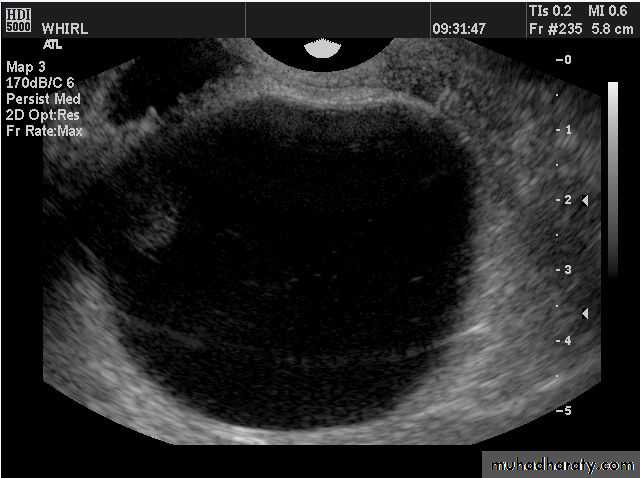

PERSISTENT ANOVULATORY FOLLICLE

Failure of ovulation and development of “cystic” follicle. The follicle typically grows larger than the mean preovulatory follicle diameter of 23 mm, thin atretic follicle walls are observed and small flecks of particulate matter are frequently seen in the lumen or aggregated at the side of the structure.